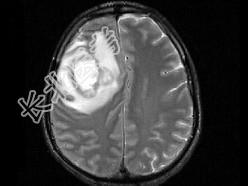

- 单项选择题男,49岁, 头痛、左侧肢体不能活动1周,PE: 左上下肢肌力O级,根据所提供图像, 最可能的诊断是 ( )

A、(右额顶)脑结核

B、(右额顶)脑转移瘤

C、(右额顶)脑脓肿

D、(右额顶)脑膜瘤

E、(右额顶)胶质瘤